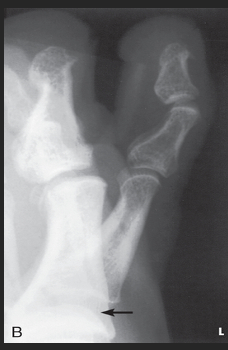

Name this projection.

Lateral calcaneus

What type of projection is it?

Mediolateral

Is the patient on the affected or unaffected side?

Affected

State specifically where the CR enters.

Perpendicular to the calcaneus // 1" distal to the medial malleolus

Which tarsal is in profile?

Calcaneus

Which radiographically significant landmark is open?

Sinus tarsi